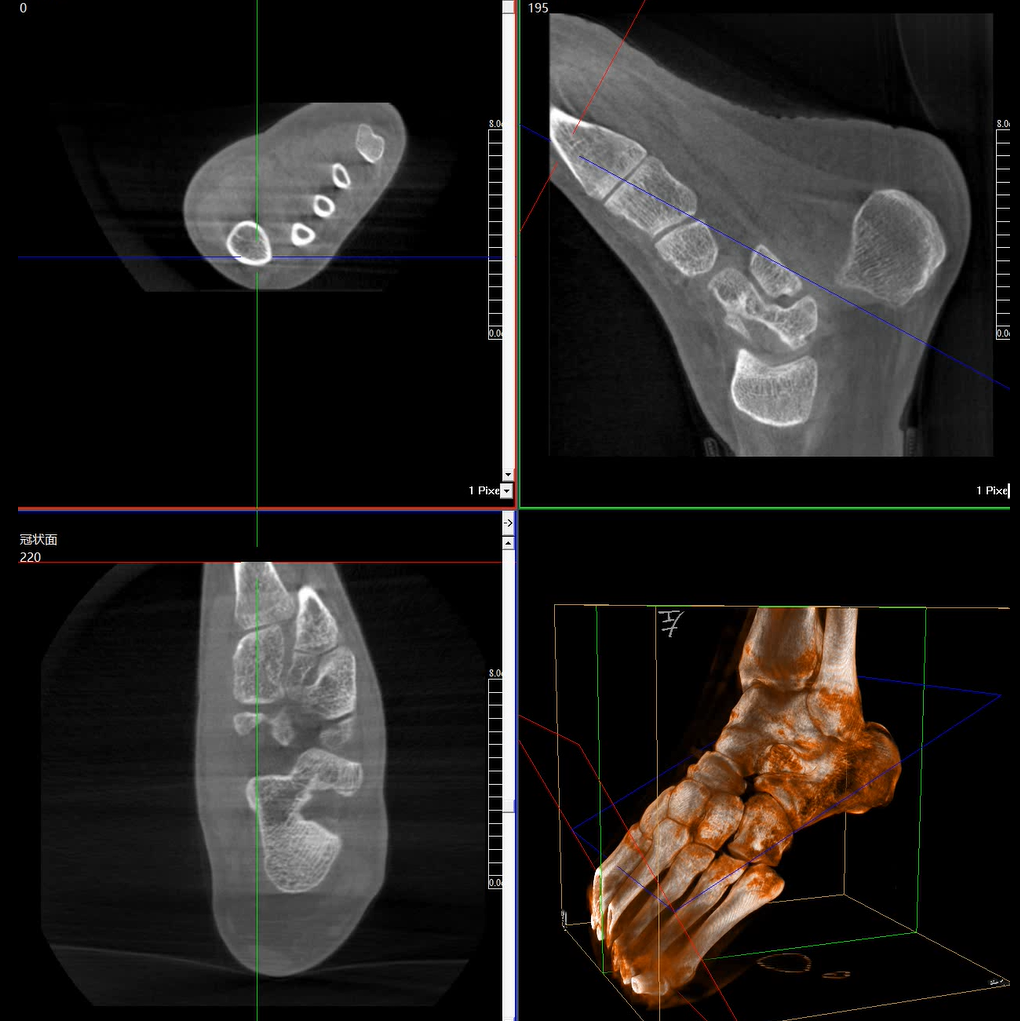

術(shù)中三維成像和橫斷面圖像提供多角度的手術(shù)診斷信息,輔助醫(yī)生進(jìn)行術(shù)中評(píng)估判斷,諸如骨折復(fù)位情況和內(nèi)植入螺釘?shù)某叽绾臀恢?,輔助手術(shù)更好地完成。

在C臂掃描過(guò)程中,始終保持拍攝主體處于射線束的中心,避免了序列圖像采集過(guò)程中的橫縱方向運(yùn)動(dòng),減少相對(duì)運(yùn)動(dòng)造成的運(yùn)動(dòng)偽影。